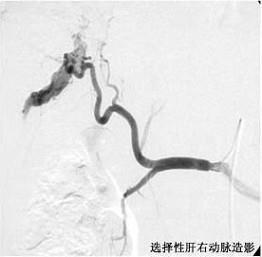

问题 诊断直径小于2cm的肝癌,最好的定位方法是 ( )

选项 A、胆道造影术 B、选择性腹腔动脉造影术 C、同位素肝扫描 D、B型超声波检查 E、肝穿刺术

答案 B